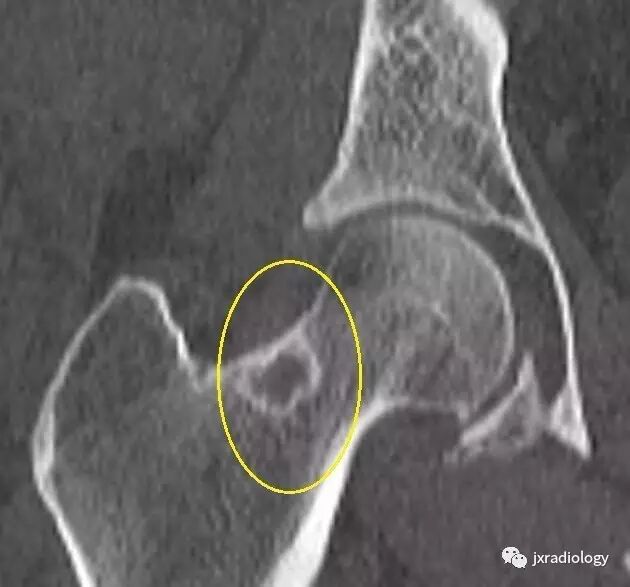

影像表现:X 线平片上表现为伴有清晰薄层硬化缘的环形(囊状)透亮区,CT 上表现为圆形 或类圆形的皮质下局灶性骨质缺损,周围见薄层硬化带环绕,边缘锐利,部分较大病灶在病灶层面或上下相邻、层面上前方显示皮质与病灶相通的局部裂隙样缺损病灶,最大径线通常小于 10 mm;MRI 示病灶在 T1WI 上呈低信号,在 T2WI 上呈均匀或不均匀高信号。

鉴别诊断:X 线平片对股骨颈疝窝具有初步诊断价值;依据典型的CT和/或MRI影像学表现,对股骨颈疝窝多可以作出准确的诊断。需要与骨内的腱鞘囊肿相鉴别:是一相邻关节的囊性病变,内衬滑膜细胞并含有粘液样物质,有时液体内蛋白质较高在T1W 上信号趋向升高。